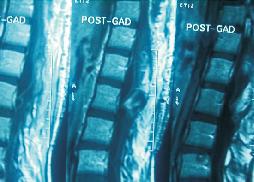

Large Conus Ependymoma